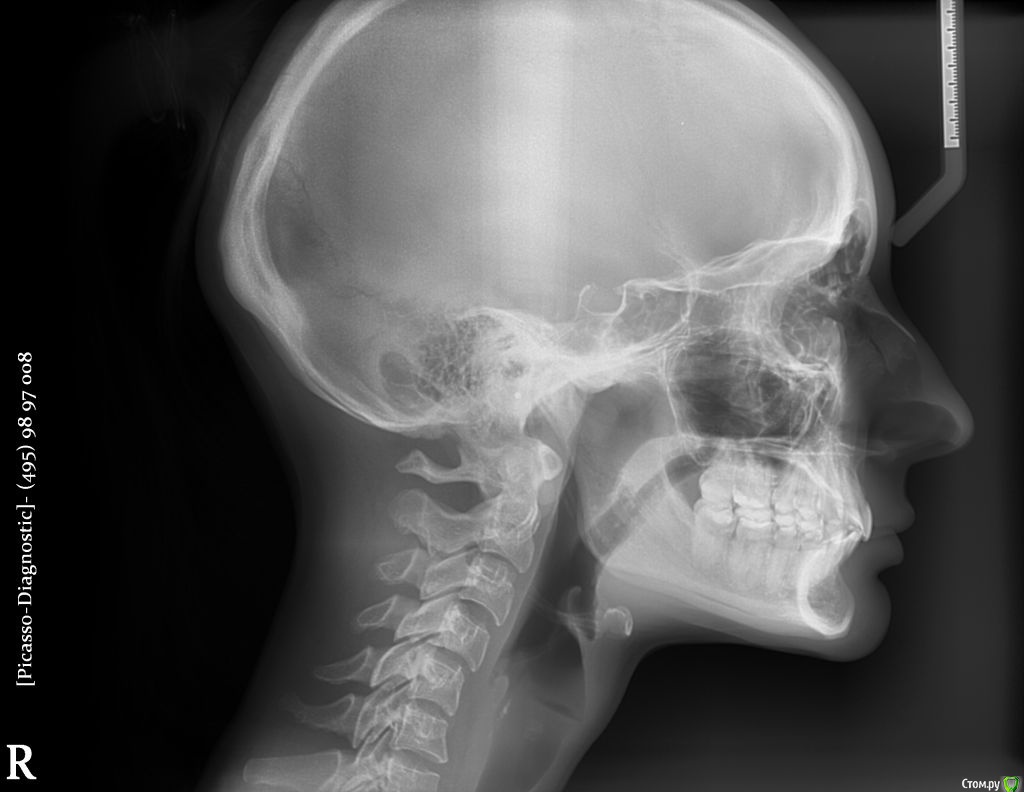

Добрый день! Очень прошу помочь с выбором врача или рекомендаций по лечению. С 2010 по 2012 год я носила брекеты (зубы были ровные, но с левой стороны верхня челюсть полностью перекрывала нижние, не было контактов, происходило стачивание). Затем с 2012 по 2016 год мне пытались исправить зубы нижней челюсти, я носила разные каппы, пластинки, то есть зубы все это время не фиксировали в определенном положении. Затем наконец в 2016-2017 году я относила полгода корректирующую каппу, которая более-менее выровняла мне нижний ряд (там была скученность). Все это время пломбы на жевательных зубах мне не меняли, они очень сильно сточились, и мне рекомендовали их заменить. Но как раз в это время у меня заболел сустав с правой стороны (на фото он соответственно слева, где и наблюдается ассиметрия). Я стала ходить по ортодонтам-ортопедам, одни говорили, что у меня все супер с прикусом, другие говорили, что клыки не под тем углом и надо снова ставить брекеты. Устав от хождений, я обратилась за диагностикой в небезызвестный центр междисдисплинарной стоматологии. Сделала там полную диагностику, по результатам которой мне предложили либо исправить брекетами клыки и поднять прикус керамическими вкладками, либо без брекетов, но тогда ставить на клыки также вкладки. Эта процедура проводится аж в три этапа и стоит как крыло самолета. Я прилагаю результаты моей диагностики. Обратилась за консультацией к другому ортопеду, который заверил, что можно обойтись временными и затем керамическими вкладками. Но помимо прикуса меня волнует ассиметрия улыбки, которая появилась в последнее время. Во-первых, я вижу невооруженным глазом, что зубы с правой стороны по высоте короче, чем с левой, то есть они меньше закрывают нижние зубы, чем с противоположной стороны, это же видно и на фото. Во-вторых, справа уголок губы при улыбке опускается как бы к низу, в отличе от левой стороны, где он идет ровно. В-третьих, с этой же правой стороны при улыбке мыщца начинается дергаться... Сейчас я уже запуталась, к какому врачу мне обращаться с данной проблемой: к ортодонту, к ортопеду, либо это гипертонус мыщц (хотя в закрытом состоянии эта ассиметрия не так заметна) Заранее благодарю за рекомендации.

Вам необходим врач-ортокраниодонт. Пытаться найти решение проблемы только на уровне зубов будет крайне трудно, да и бесполезно. Это сравнимо с симптоматическим лечением, когда идёт борьба только с симптомами заболевания, но никак не влияя на главную причину. Природа Ваших проблем (ДВНЧС, асимметрия) кроется в черепе, а точнее, в имеющимся его искажении